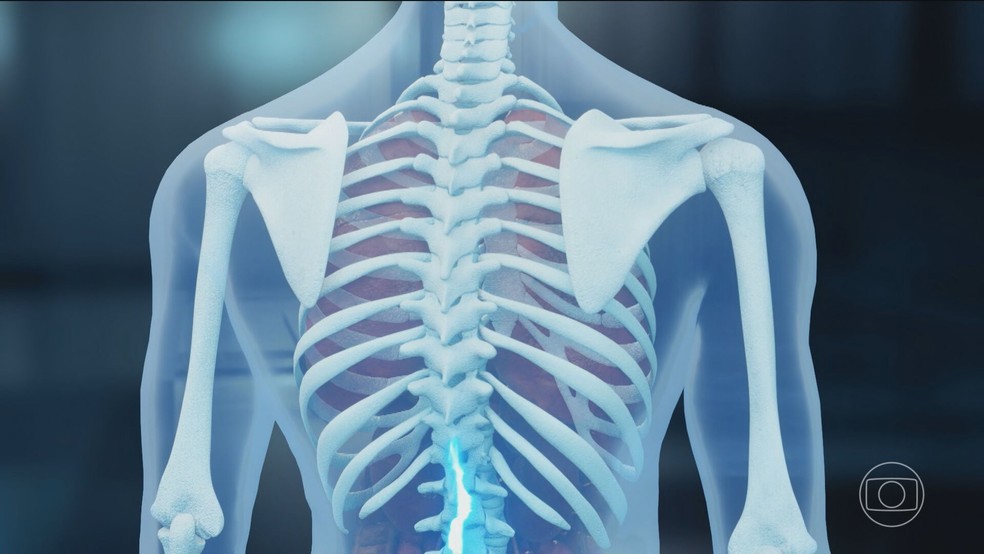

Um novo medicamento desenvolvido no Brasil, a partir de uma proteína extraída da placenta, está mostrando resultados promissores ao restaurar movimentos em pessoas que sofreram paralisia por lesão na medula espinhal.

O tratamento inédito, que ainda está em fase experimental, se baseia na ação da proteína polilaminina, que ajuda a regenerar os neurônios danificados.

A paralisia ocorre quando os axônios, parte dos neurônios responsáveis por conduzir impulsos elétricos, se rompem devido à lesão na medula.

Os pesquisadores descobriram que, ao ser multiplicada, a polilaminina pode atuar diretamente na área lesionada, auxiliando na recuperação.